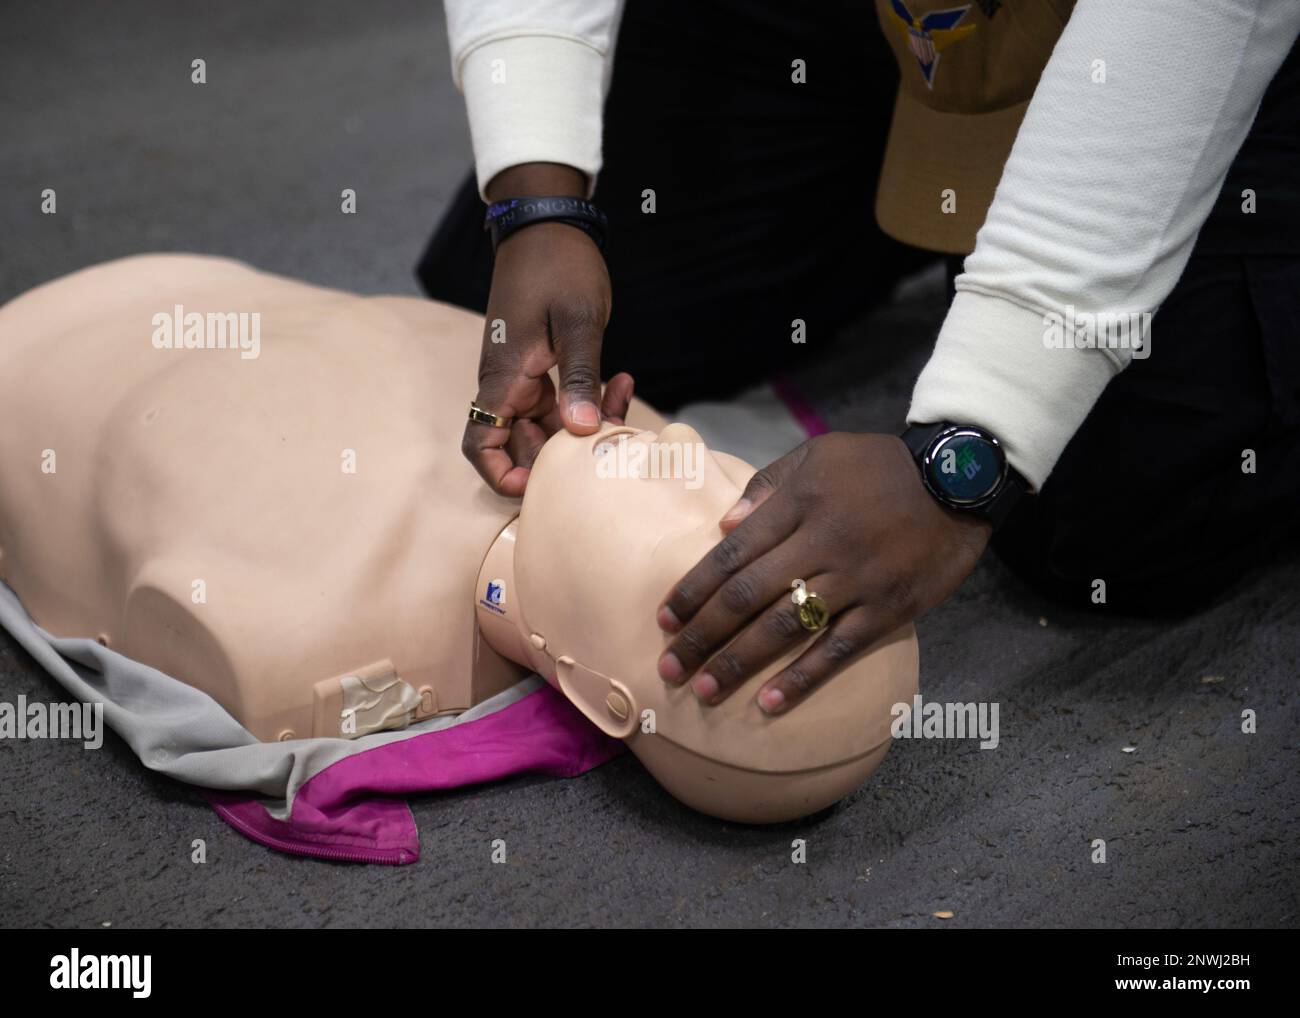

230118-N-MD461-1043 PACIFIC OCEAN (Jan. 18, 2022) Hospital Corpsman 3rd Class Ahmi Atsina, a native of New Orleans, La., instructs Sailors how to check for airway obstruction during CPR training in the jet shop aboard Nimitz-class aircraft carrier USS Carl Vinson (CVN 70). Vinson is currently underway conducting routine maritime operations. Stock Photohttps://www.alamy.com/image-license-details/?v=1https://www.alamy.com/230118-n-md461-1043-pacific-ocean-jan-18-2022-hospital-corpsman-3rd-class-ahmi-atsina-a-native-of-new-orleans-la-instructs-sailors-how-to-check-for-airway-obstruction-during-cpr-training-in-the-jet-shop-aboard-nimitz-class-aircraft-carrier-uss-carl-vinson-cvn-70-vinson-is-currently-underway-conducting-routine-maritime-operations-image532074469.html

230118-N-MD461-1043 PACIFIC OCEAN (Jan. 18, 2022) Hospital Corpsman 3rd Class Ahmi Atsina, a native of New Orleans, La., instructs Sailors how to check for airway obstruction during CPR training in the jet shop aboard Nimitz-class aircraft carrier USS Carl Vinson (CVN 70). Vinson is currently underway conducting routine maritime operations. Stock Photohttps://www.alamy.com/image-license-details/?v=1https://www.alamy.com/230118-n-md461-1043-pacific-ocean-jan-18-2022-hospital-corpsman-3rd-class-ahmi-atsina-a-native-of-new-orleans-la-instructs-sailors-how-to-check-for-airway-obstruction-during-cpr-training-in-the-jet-shop-aboard-nimitz-class-aircraft-carrier-uss-carl-vinson-cvn-70-vinson-is-currently-underway-conducting-routine-maritime-operations-image532074469.htmlRM2NWJ2BH–230118-N-MD461-1043 PACIFIC OCEAN (Jan. 18, 2022) Hospital Corpsman 3rd Class Ahmi Atsina, a native of New Orleans, La., instructs Sailors how to check for airway obstruction during CPR training in the jet shop aboard Nimitz-class aircraft carrier USS Carl Vinson (CVN 70). Vinson is currently underway conducting routine maritime operations.

230118-N-MD461-1043 PACIFIC OCEAN (Jan. 18, 2022) Hospital Corpsman 3rd Class Ahmi Atsina, a native of New Orleans, La., instructs Sailors how to check for airway obstruction during CPR training in the jet shop aboard Nimitz-class aircraft carrier USS Carl Vinson (CVN 70). Vinson is currently underway conducting routine maritime operations. Stock Photohttps://www.alamy.com/image-license-details/?v=1https://www.alamy.com/230118-n-md461-1043-pacific-ocean-jan-18-2022-hospital-corpsman-3rd-class-ahmi-atsina-a-native-of-new-orleans-la-instructs-sailors-how-to-check-for-airway-obstruction-during-cpr-training-in-the-jet-shop-aboard-nimitz-class-aircraft-carrier-uss-carl-vinson-cvn-70-vinson-is-currently-underway-conducting-routine-maritime-operations-image553329917.html

230118-N-MD461-1043 PACIFIC OCEAN (Jan. 18, 2022) Hospital Corpsman 3rd Class Ahmi Atsina, a native of New Orleans, La., instructs Sailors how to check for airway obstruction during CPR training in the jet shop aboard Nimitz-class aircraft carrier USS Carl Vinson (CVN 70). Vinson is currently underway conducting routine maritime operations. Stock Photohttps://www.alamy.com/image-license-details/?v=1https://www.alamy.com/230118-n-md461-1043-pacific-ocean-jan-18-2022-hospital-corpsman-3rd-class-ahmi-atsina-a-native-of-new-orleans-la-instructs-sailors-how-to-check-for-airway-obstruction-during-cpr-training-in-the-jet-shop-aboard-nimitz-class-aircraft-carrier-uss-carl-vinson-cvn-70-vinson-is-currently-underway-conducting-routine-maritime-operations-image553329917.htmlRM2R469XN–230118-N-MD461-1043 PACIFIC OCEAN (Jan. 18, 2022) Hospital Corpsman 3rd Class Ahmi Atsina, a native of New Orleans, La., instructs Sailors how to check for airway obstruction during CPR training in the jet shop aboard Nimitz-class aircraft carrier USS Carl Vinson (CVN 70). Vinson is currently underway conducting routine maritime operations.